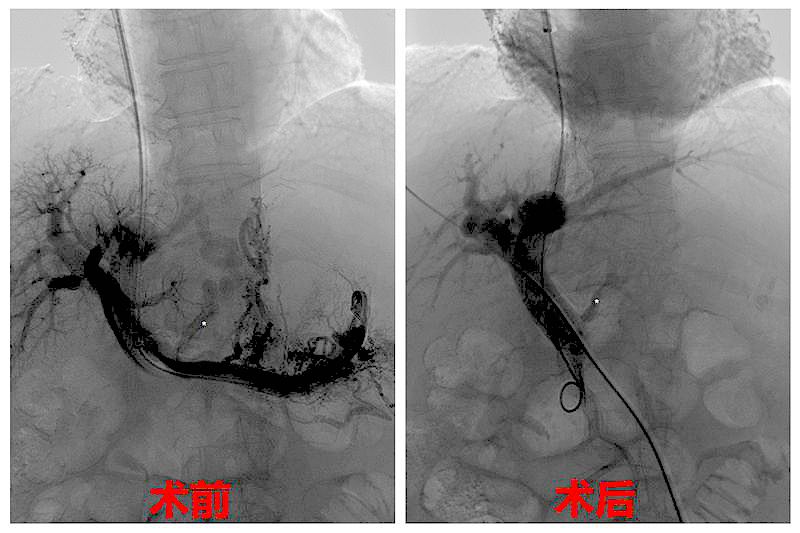

7月27日下午,在温医大附一院消化科副主任医师吴伟的带领下,我院影像科副主任郑胜、主治医师苏维杰共同在数字减影血管造影机导引下,为老人实施TIPS术。

术中,医生在患者的右侧颈部的静脉为穿刺入口,将导管置入肝门静脉内,经过测量患者门静脉压力达到34cmH2O,比正常人高出一倍多;当医生将支架植入肝静脉与门静脉之间建立起人工分流通道后,门静脉压力逐渐恢复到正常人的水平。

术后造影显示支架分流道血流通畅,老人腹胀症状明显改善,腹水减少,恢复情况良好。